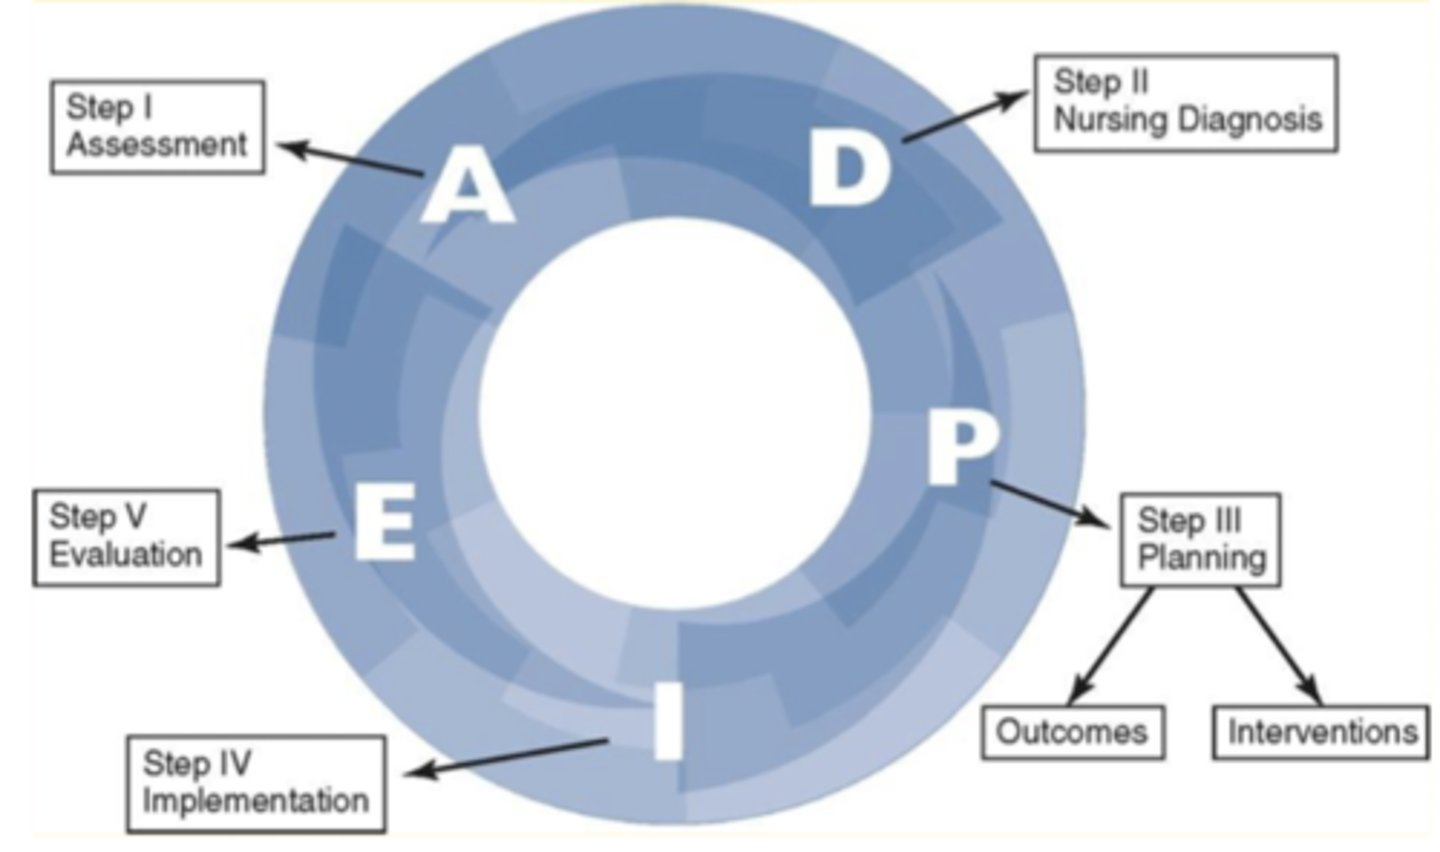

Nursing Process

A problem solving approach to identifying and treating client problems (ADPIE)

ADPIE

- Assessment

- Diagnosis

- Planning

- Implementation

- Evaluation

Assessment

Diagnosis

Planning

Implementation

Evaluation